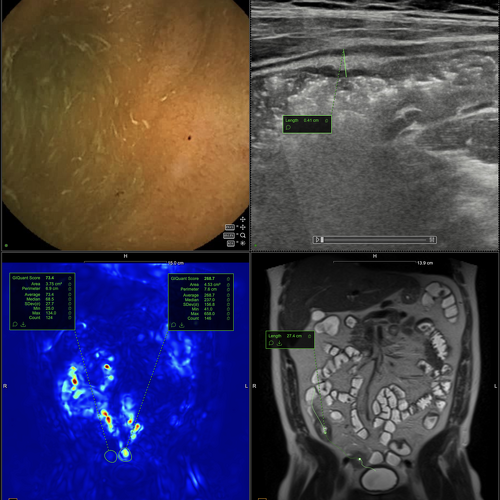

Affecting up to 30-40% of patients, they are associated with pain, leakage, and repeated interventions, often persisting for years despite intensive medical and surgical treatment. For patients, this means a profound impact on quality of life and daily functioning. For clinicians and researchers, it remains an area of urgent unmet need — where innovation in therapies, imaging, and outcome measures is essential to move care forward.

Achieving fistula closure while preserving continence remains difficult.

Even after surgical intervention or biologic therapy, recurrence rates remain high.

Together, these approaches aim to standardise assessment, improve clinical trial design, and accelerate the development of new therapies.